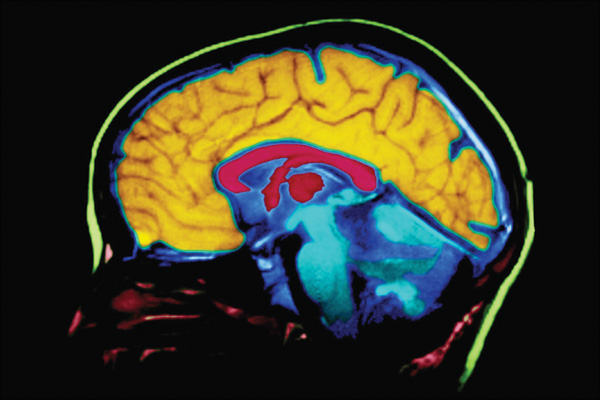

In this study, scientists conducted a trial in mouse models of Alzheimer’s disease of bexarotene, with the goal of enhancing clearance of beta amyloid from the brain by increasing levels of ApoE protein. The scientists found that the orally-administered drug rapidly lowered levels of soluble beta amyloid and amyloid plaques in both young and older test animals, and also improved some cognitive and behavioral deficits.

Scientists orally administered the bexarotene to mouse models that had been bred with Alzheimer’s disease. They then observed changes in mouse behavior and the levels of beta amyloid in the brain after delivery of the drug.